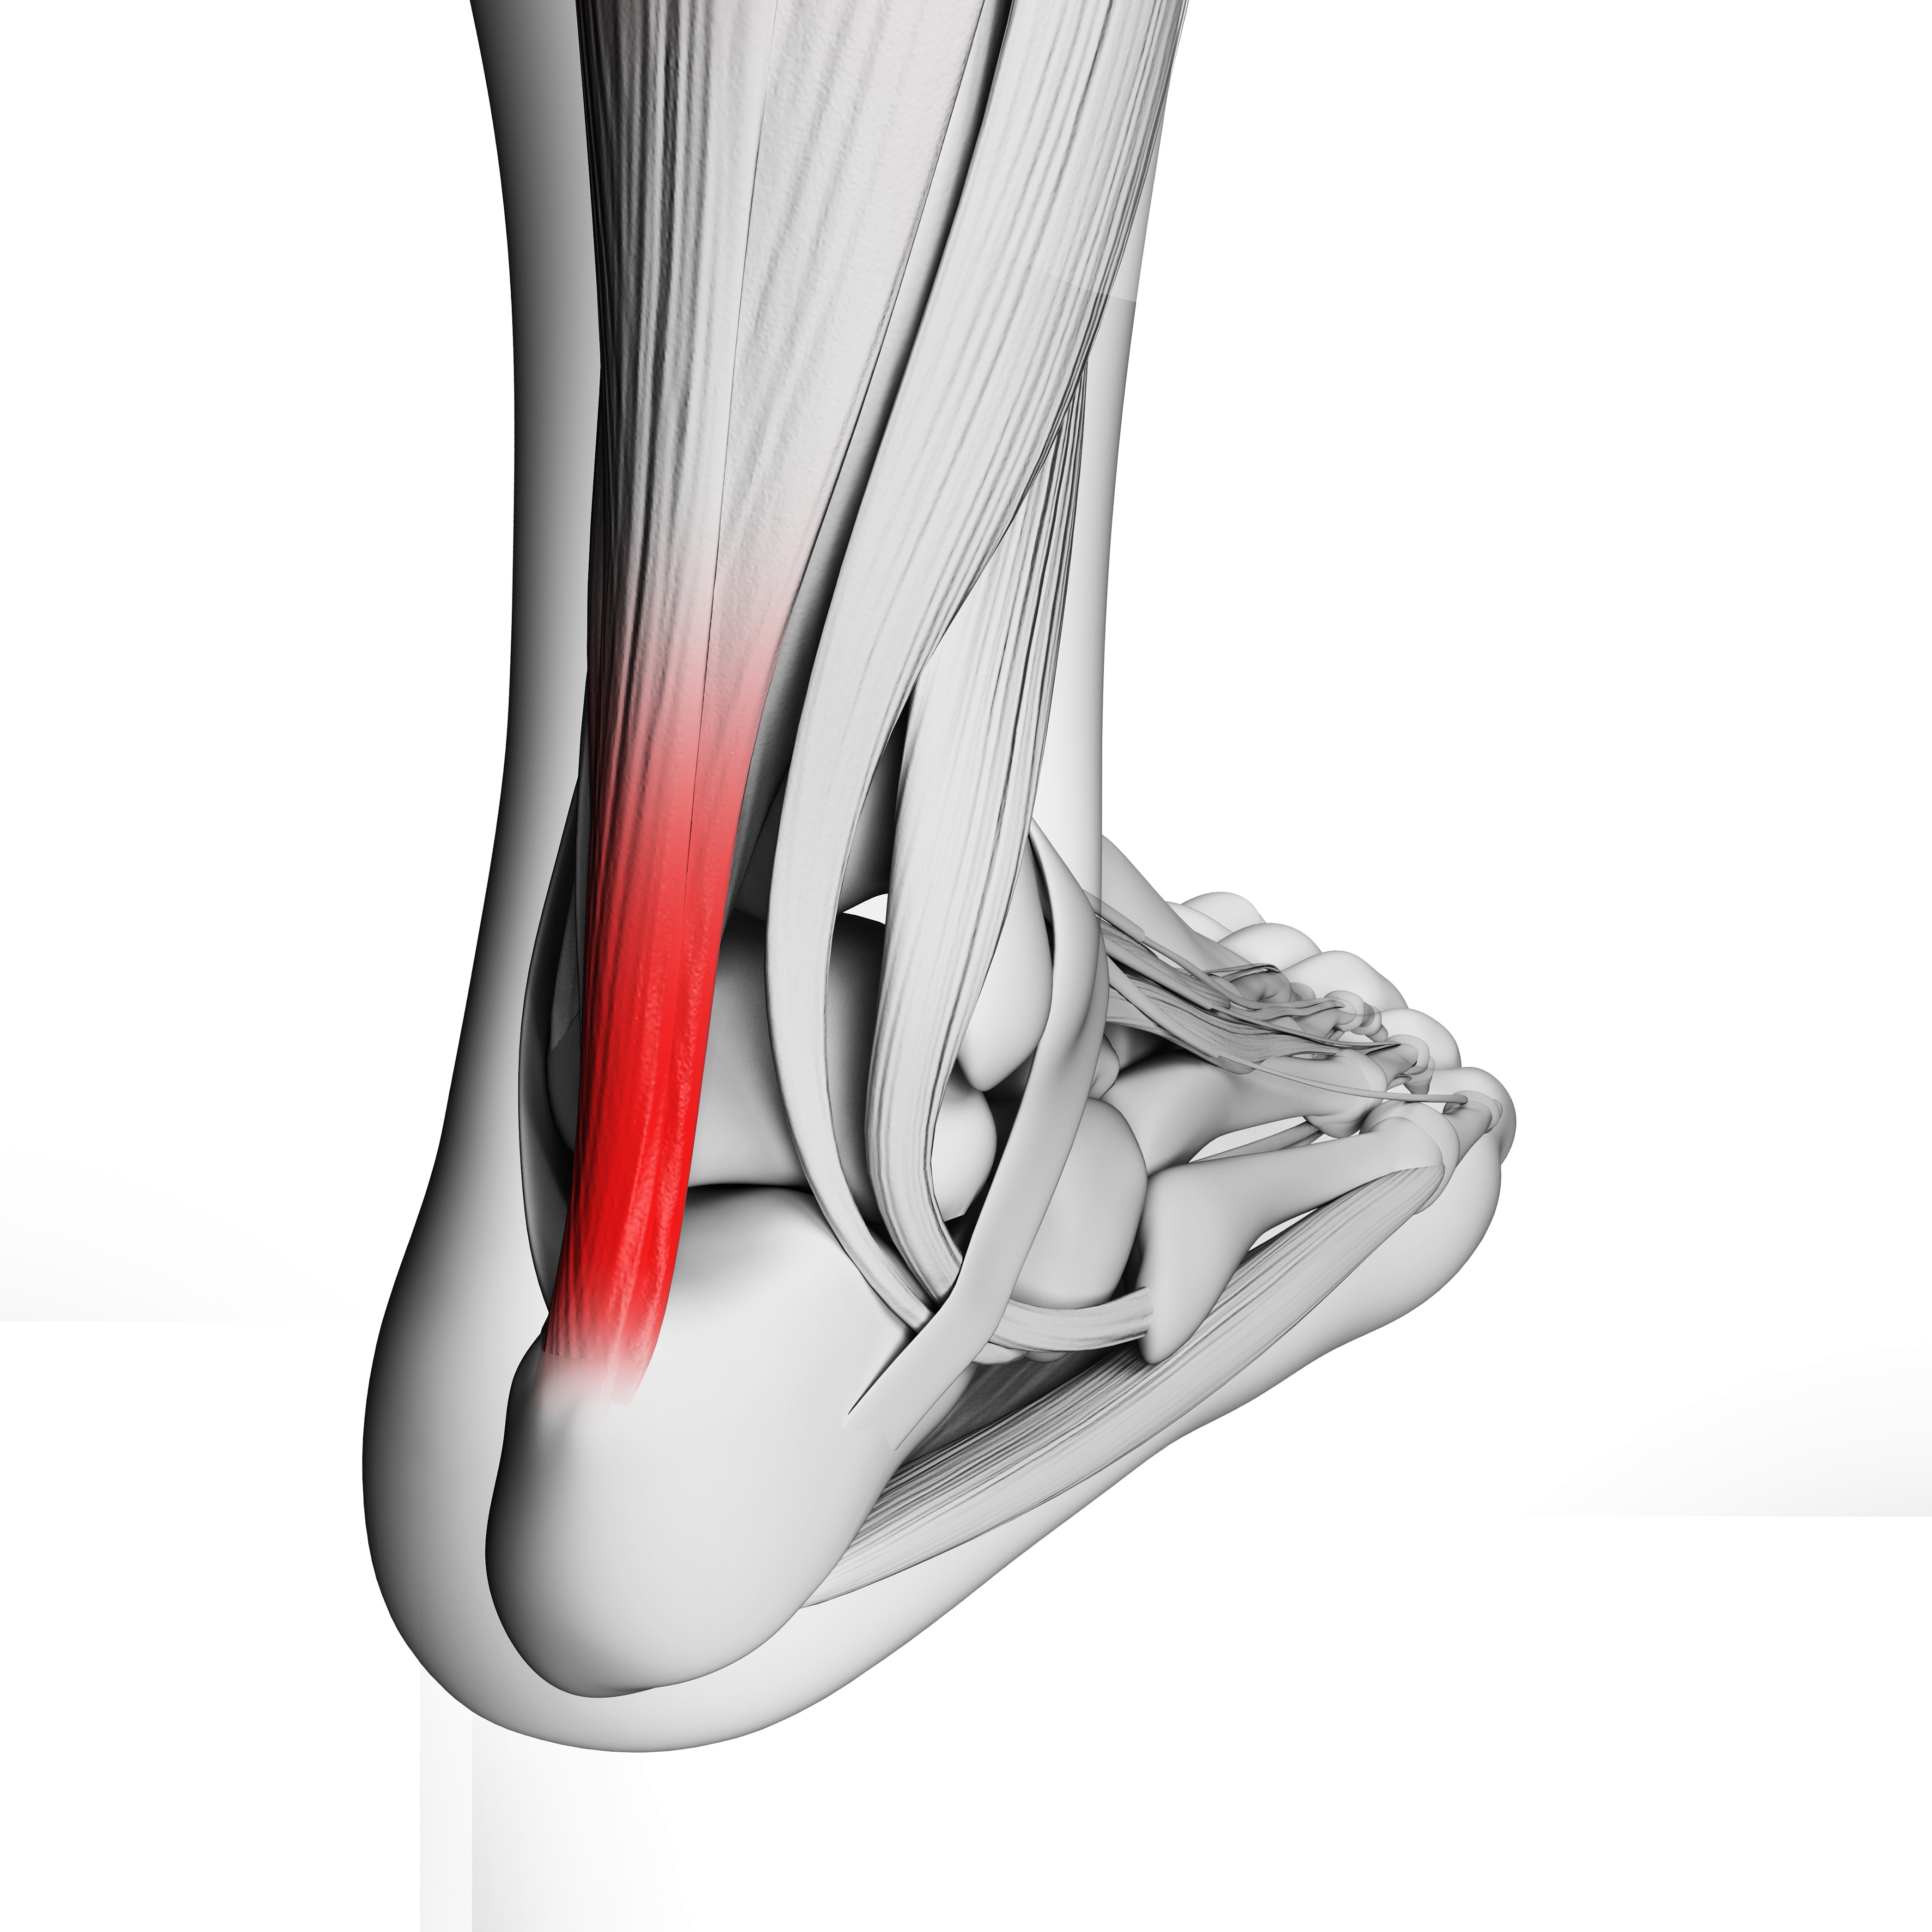

아킬레스건병원 파열 후 봉합을 못할 경우 해결방법은? 아킬레스건은 발뒷꿈치와 종아리근육을 연결하는 중요한 부분으로, 부상 시 치명적인 영향을 미칠 수 있는

아킬레스건손상: 수술이 반드시 필요한가? 아킬레스건손상은 스포츠 부상이나 일상생활에서 발생할 수 있는 흔한 문제 중 하나입니다. 이 손상은 아킬레스건이 부서지거나 끊어지는

아킬레스건염의 원인 아킬레스건염은 아킬레스건 주변의 염증으로 일반적으로 운동을 할 때 발생합니다. 대표적인 원인은 과도한 운동이나 부상으로 인한 스트레스가 있습니다. 또한,